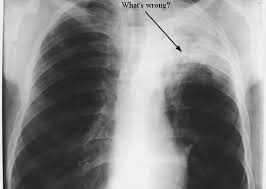

There are some symptoms of lung cancer in Oklahoma City to watch for. If you have a persistent cough, see your doctor. If you have difficulty breathing, you should also talk to your doctor. They will conduct an x-ray or MRI to be able to see if you have any cancer on your lungs. If cancer is found, treatment options include chemotherapy and radiation. When caught early, you can survive lung cancer. If the cancer is advanced, you may have to undergo more aggressive chemotherapy treatments. Your doctor will also check to make sure the cancer has not spread to other organs in the body. Be sure to listen to your doctor and follow his or her treatment regimen. Doing so may save your life.